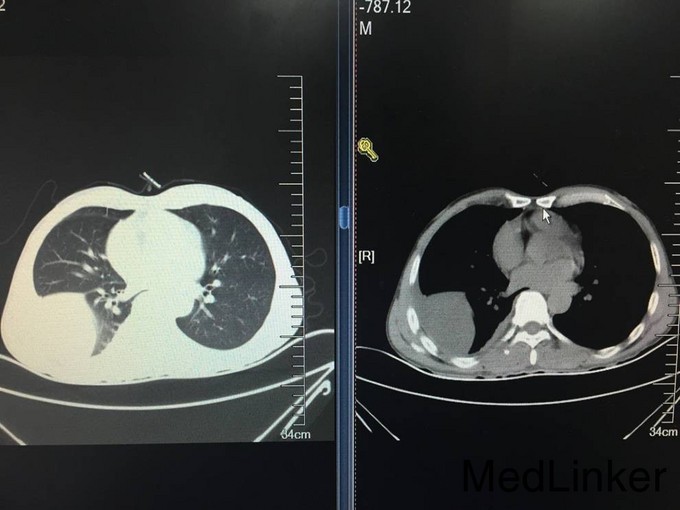

患者老年男性,以“胸闷气短8天”为主诉入院。 患者8天前无明显诱因出现胸闷气短,活动时加重,伴间断咳嗽咳痰,痰为白痰,伴间断发热,体温最高38.8℃,无发冷及寒战,夜间盗汗明显。自行口服阿莫西林、阿奇霉素等药物,症状未见明显缓解,遂就诊于沈阳市第五医院。行肺CT检查,提示:右侧胸腔包裹下积液并左肺下叶膨胀不全,建议进一步检查及复查。左肺上叶陈旧病变。血常规未提示白细胞及中性粒细胞百分比水平升高。患者病来无头晕头痛,无胸痛咯血,无恶心呕吐。食睡眠差,大小便如常,体重未见明显减轻

查体:T:37.5℃,BP:105/80mmHg,P:80次/分,R:18次/分;神清语明,步入病房,查体合作,睑结膜无苍白,口唇无发绀,浅表淋巴结未触及肿大,咽无充血,扁桃体未见肿大,颈软,气管居中,颈静脉无怒张。双肺听诊呼吸音粗,右侧下肺野呼吸音消失,双肺未闻及明显干湿啰音。心界不大,心音钝,节律齐,心率80次/分,各瓣膜听诊区未闻及杂音。全腹软,无压痛,无反跳痛及肌紧张,肝脾肋下未触及,肝肾区无叩痛,无杵状指,双下肢无水肿。 CRP:137.0mg/L。血常规:白细胞计数 6.7*10^9/L,中性粒细胞百分比 70.8%,血红蛋白115g/L,血小板计数 356*10^9/L。降钙素原检测:降钙素原 0.065ng/mL。军团菌、结核抗体、支原体抗体、衣原体抗体均阴性。凝血五项:凝血酶原时间 13.80秒,纤维蛋白原含量 5.84g/L,D-dimer 1101ug/L。一般细菌涂片检查:细菌涂片结果。呼吸道正常菌群。1-3-β-D葡聚糖定量检测:132.8。甲功系列、肺癌系列无异常。生化:总蛋白 54.1g/L,白蛋白 32.5g/L,前白蛋白 0.07g/L,血糖5.01mmol/L,痰结核培养均阴性,患者未成功留取痰结核菌涂片化验。患者入院第二日请介入科会诊,行右侧胸腔穿刺引流术,留置右侧胸腔引流管一枚,引流淡黄色透明液体,引流第一天引流液体800ml,将引流管夹闭,引流液留取化验。胸水化验回报:LDH:乳酸脱氢酶 583;胸腹水常规检查:李凡他试验 阳性(+);白细胞计数 2.89210^9/L;单个核细胞百分比 96.2%;体液ADA:腺苷脱氨酶 61U/L;细菌培养:培养结果 未见细菌生长。胸水结核菌涂片及结核菌培养均阴性。血T-SPOT:混合淋巴细胞培养 50细胞数;A抗原刺激+γ-干扰素 11SFCs/2.5*105PBMC;B抗原刺激+γ-干扰素 6SFCs/2.5*105PBMC。患者胸水病理检查未查见肿瘤细胞。目前患者化验结果提示胸水ADA水平较高,胸水李凡他试验阳性,胸水淋巴细胞比例较高,考虑患者结核性胸水可能性大。患者近日流量管未见引流液流出,复查肺CT,结果:右肺上叶结节,性质待定。右侧胸腔积液,叶间包裹性积液,右肺下叶部分受压不张。左肺上叶钙化灶,双肺散在慢性炎症。心包积液。右侧心膈角淋巴结稍增大。左肾低密度影,必要时进一步检查。请胸科医院会诊,考虑患者结核胸膜炎可能性大,建议转入胸科医院行诊断性抗结核治疗,同时反复胸水病理检查除外恶性。